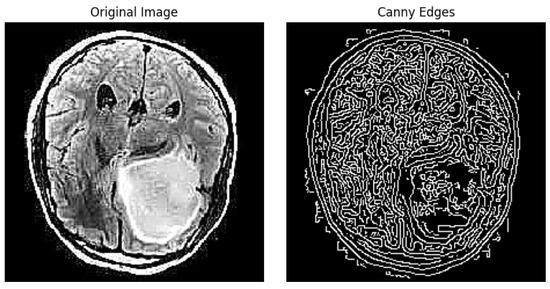

After this step, this technique involves thinning the edges to a single pixel width, iterating over all pixels in the gradient magnitude image and suppressing the gradient values of all pixels except the local maxima in the direction of the gradient. The result of this technique is similar, as shown in Figure 5.

Figure 5. Edge detection example using canny filter.

Jimaging 10 00232 g005